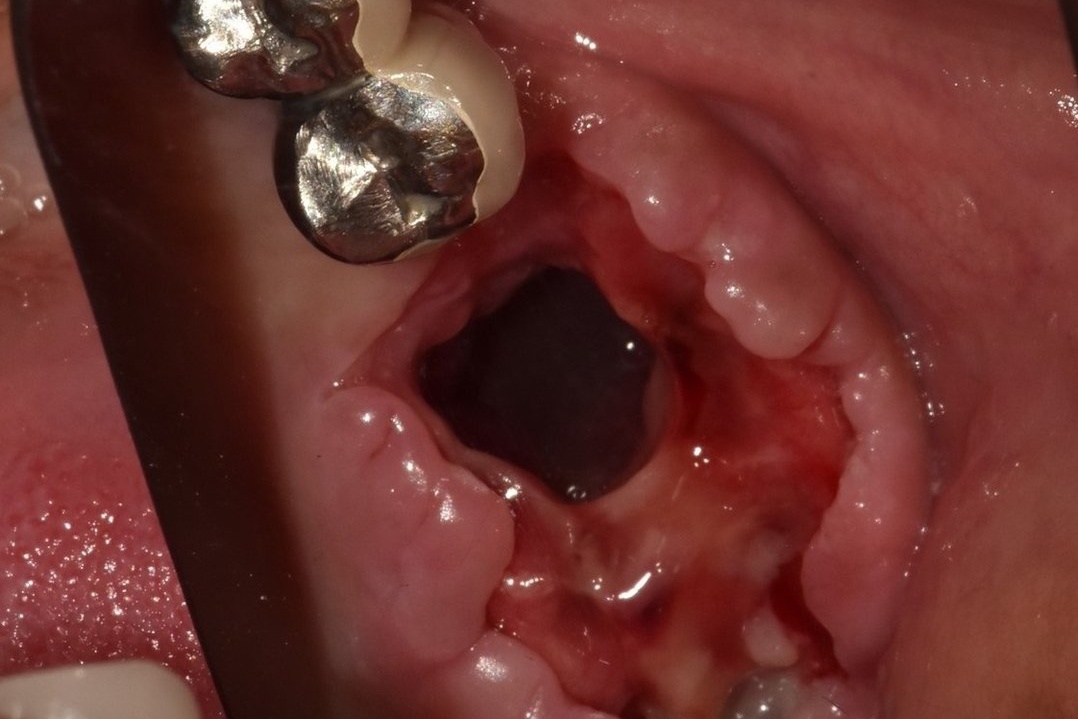

상악동 누공 폐쇄술

상악동 누공은 입과 코가 개통되는 증상입니다.

• 상악동 거상술이나 염증이 심한 상악의 치아를 발치하는 경우 속발성으로 상악동 누공이라는 증상이 생길수 있습니다.

• 이 증상은 구강에서 생긴 구멍이 상악동에 연결되어 막히지 않는 질환으로 물을 마시면 코로 물이 흐르는 등의 일상 생활에 상당한 불편을 초래합니다.

• 이러한 누공을 폐쇄시키는 수술은 상당한 전문적 기술과 경험을 필요로 하며 구강외과의 전문 분야로서 전문의의 진료 및 적절한 폐쇄 수술이 필요합니다.

• 누공이 적절하게 폐쇄된 이후에는 치아의 수복을 위해 치조골 이식과 임플란트 수술이 동반되는 경우가 많습니다.

상악동 누공 폐쇄 케이스

안녕하세요. 내인생치과 신창훈입니다. 이번에 소개해 드릴 환자분은 발치후 상악동이 천공 되어서 입안의 물이 코로 들어가고 코로 바람이 새는 증상이 있어서 발치한 치과에서 비흡수성 차폐막으로 막은 상태로 오셨습니다. 저희 치과에 오신 거는 발치한 날로부터 약 3주가 지난 상태로 오셨는데 발치한 치과에서는 한달이 안 되었기 때문에 더 기다려 볼 것을 권유 받…